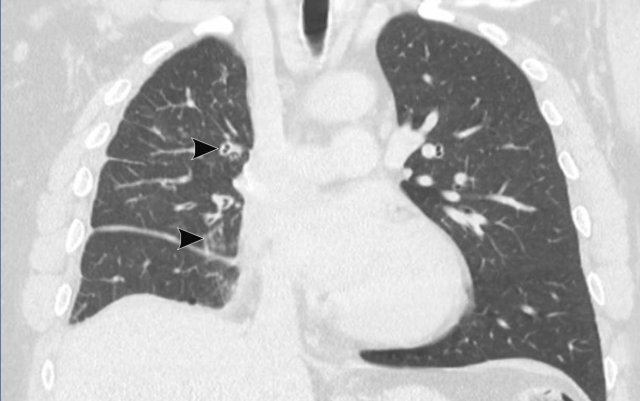

Image

Tracheobronchial

papillomatosis with lung involvement in a 54 y.o male, showing two papillomas

in the trachea.

Continue with the lung window...

The image shows multiple cystic lesions in both lungs (arrowheads).

In rare cases extension into the lung parenchyma can occur, showing cystic nodules most often in the dependent apical segments of the lower lobes. There is a small risk of malignant transformation from squamous cell papilloma into squamous cell carcinoma.